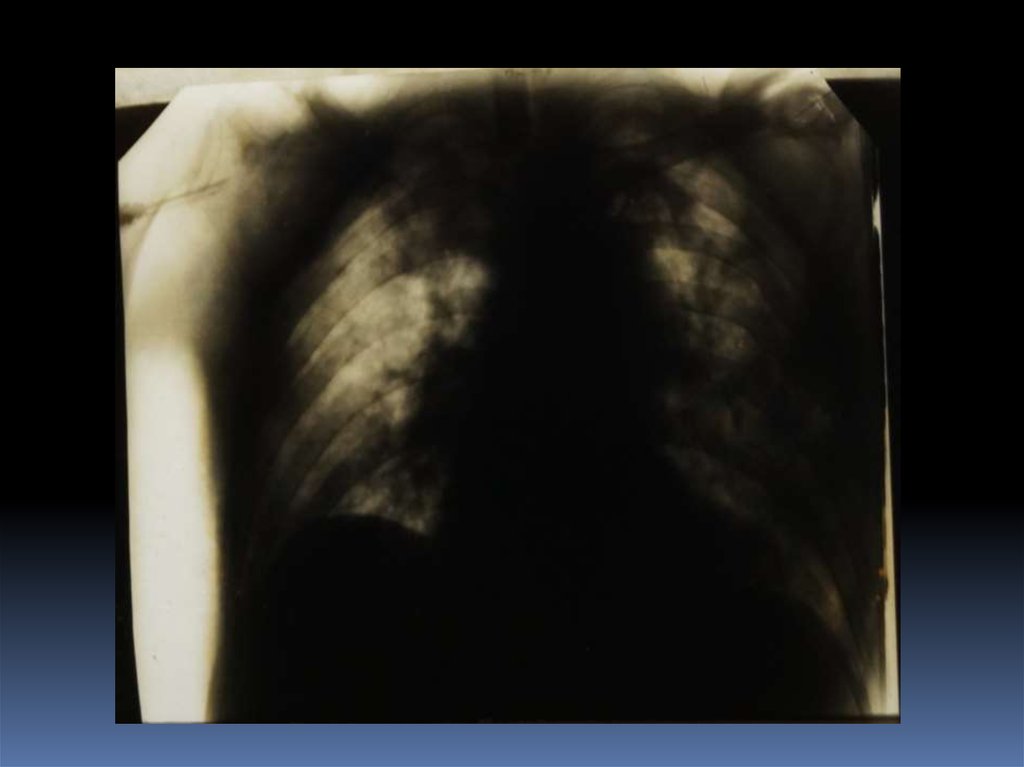

5. Проведение рентгеноскопического исследования раненого.

6. Проведение рентгенографического исследования раненого.

7. Виды травматического повреждения грудной клетки:

пневмоторакс;

гемоторакс;

гемопневмоторакс;

внутрилегочные гематомы;

дисковидные ателектазы;

посттравматические пневмонии.